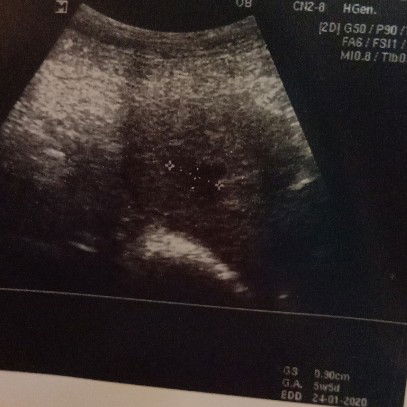

rse skjap jr mase berlalu ... taun lpas 29.5 baru kehilangan kandungan pertama.. dengan kuasa Allah setahun kemudian saya bakal melahirkan anak pertama... due date saya dijangka 2.6 ni lpas raya #baby raya 2020 siapa lgi yg due dy hampir2 dgn raya .. mencabar sikit la waktu berpantang kite apa2 pon semoga baby kite smua slamat dilahirkan ckop sifat insya allah .. amin